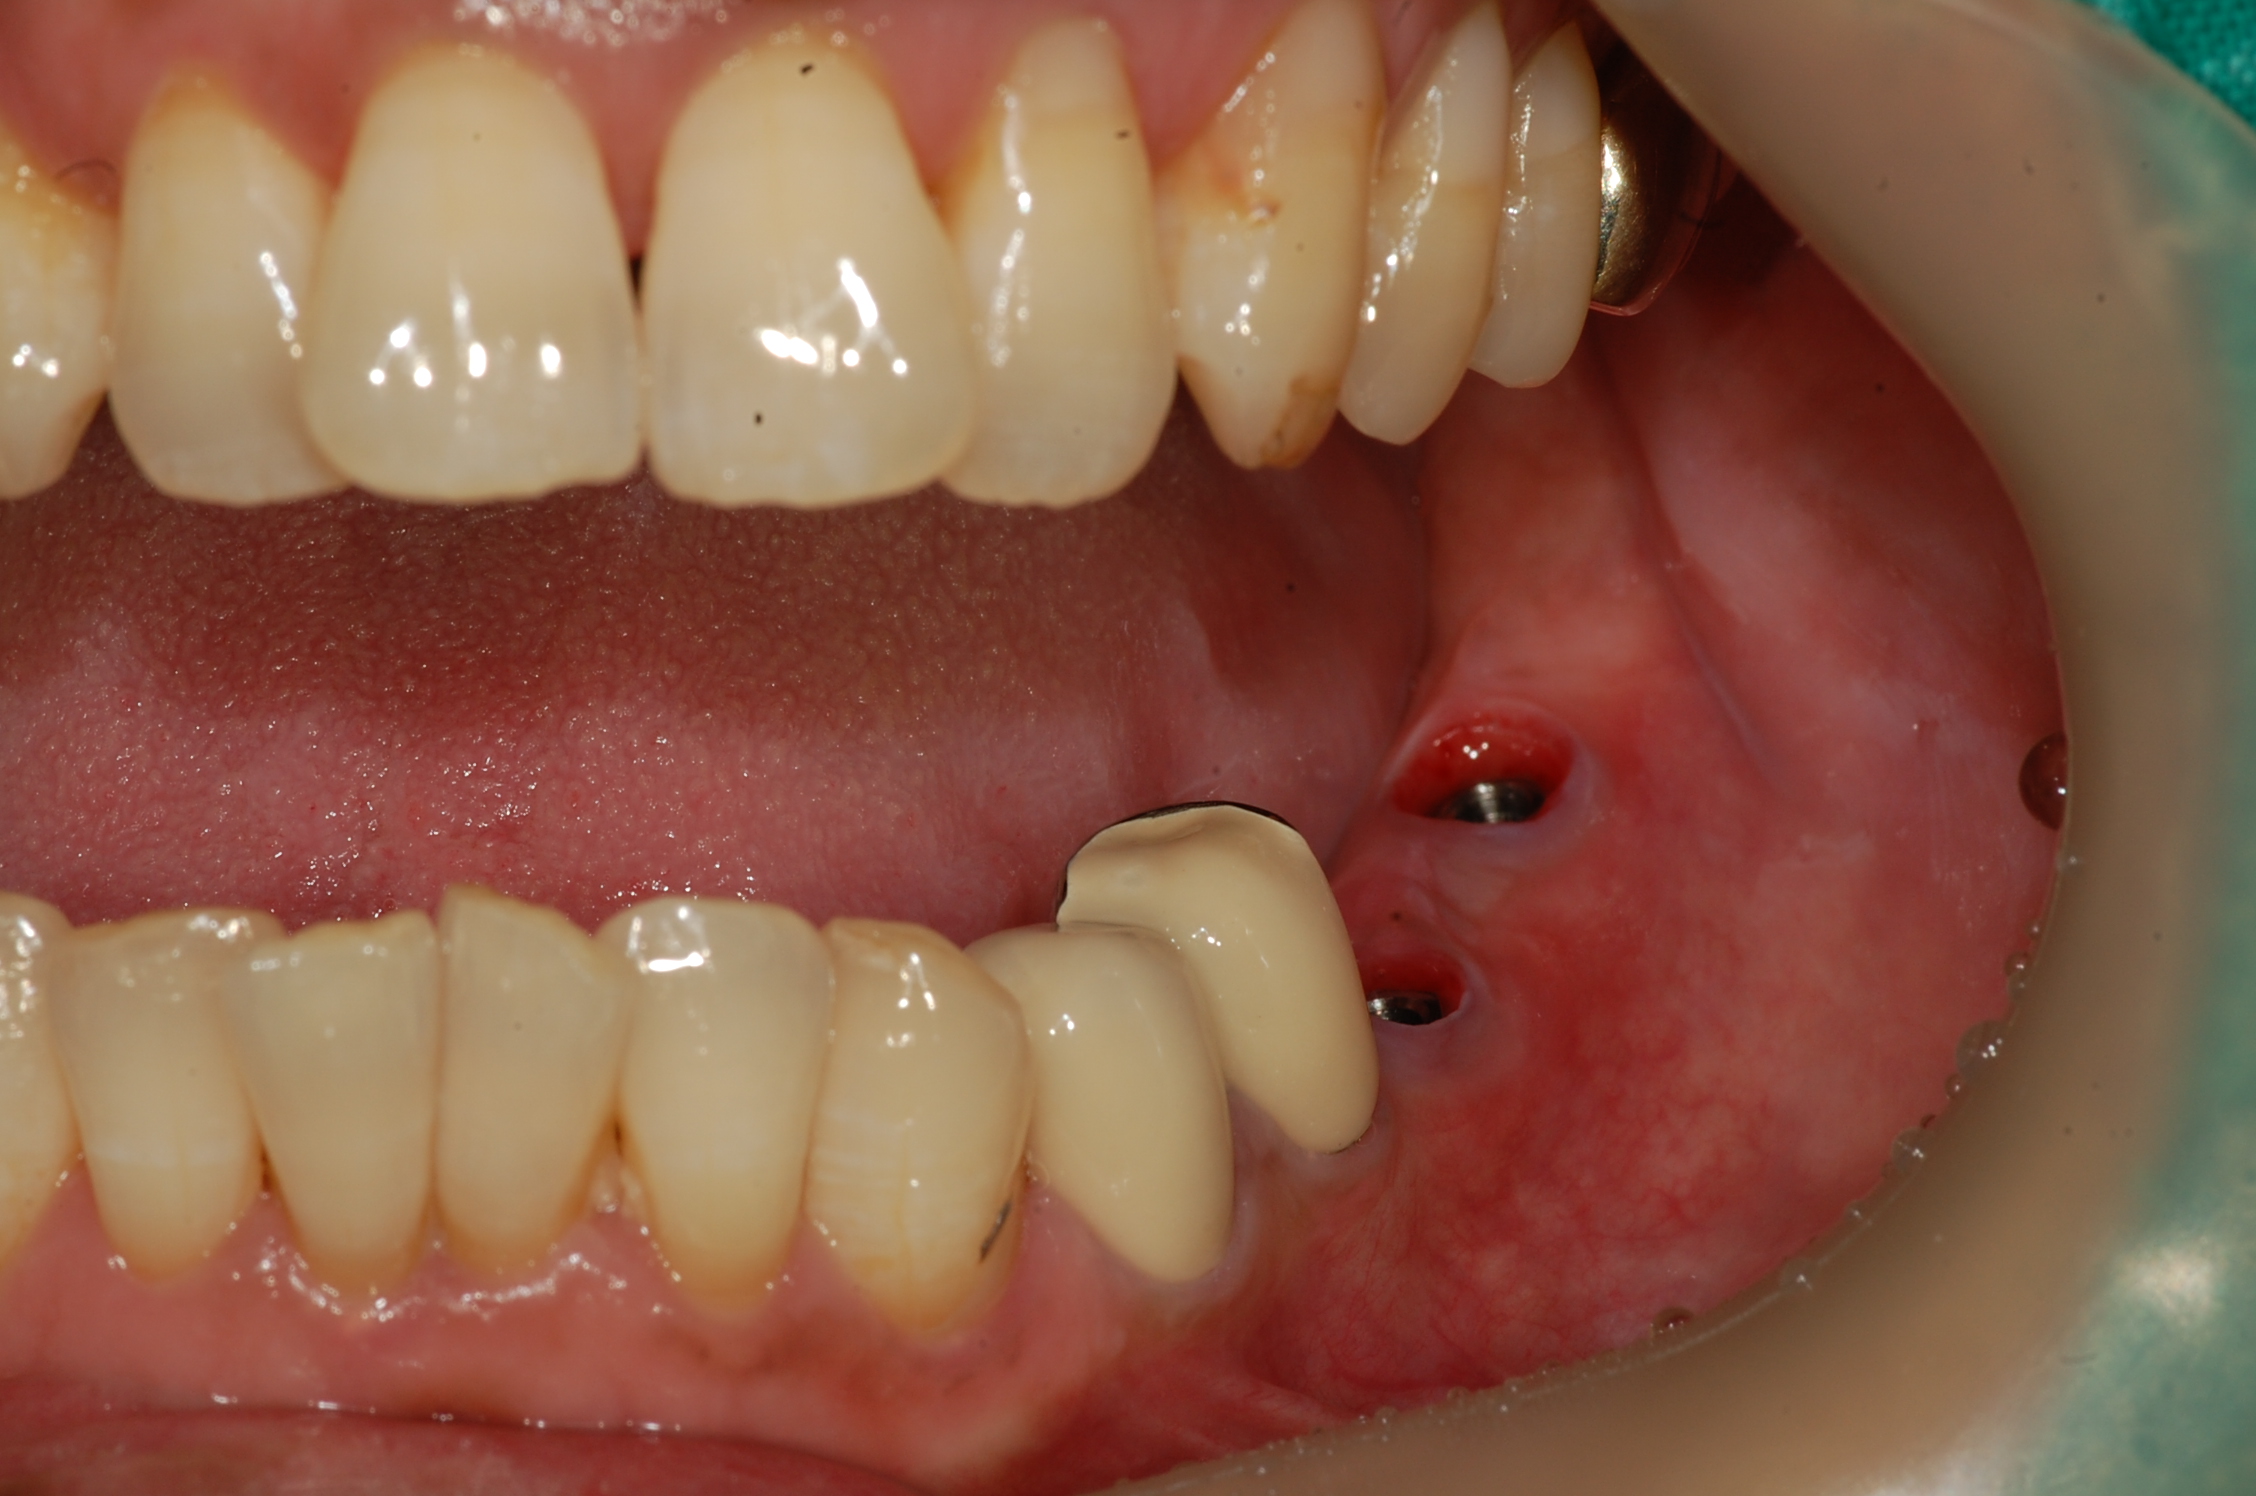

[임플란트] 제목 : 하악구치부

임플란트 및 보철치료